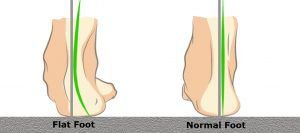

Flat foot is a condition in which the the medial or internal arch of the foot shrinks or totally disappears.

In children with flat foot, the arch of the feet disappear when standing.